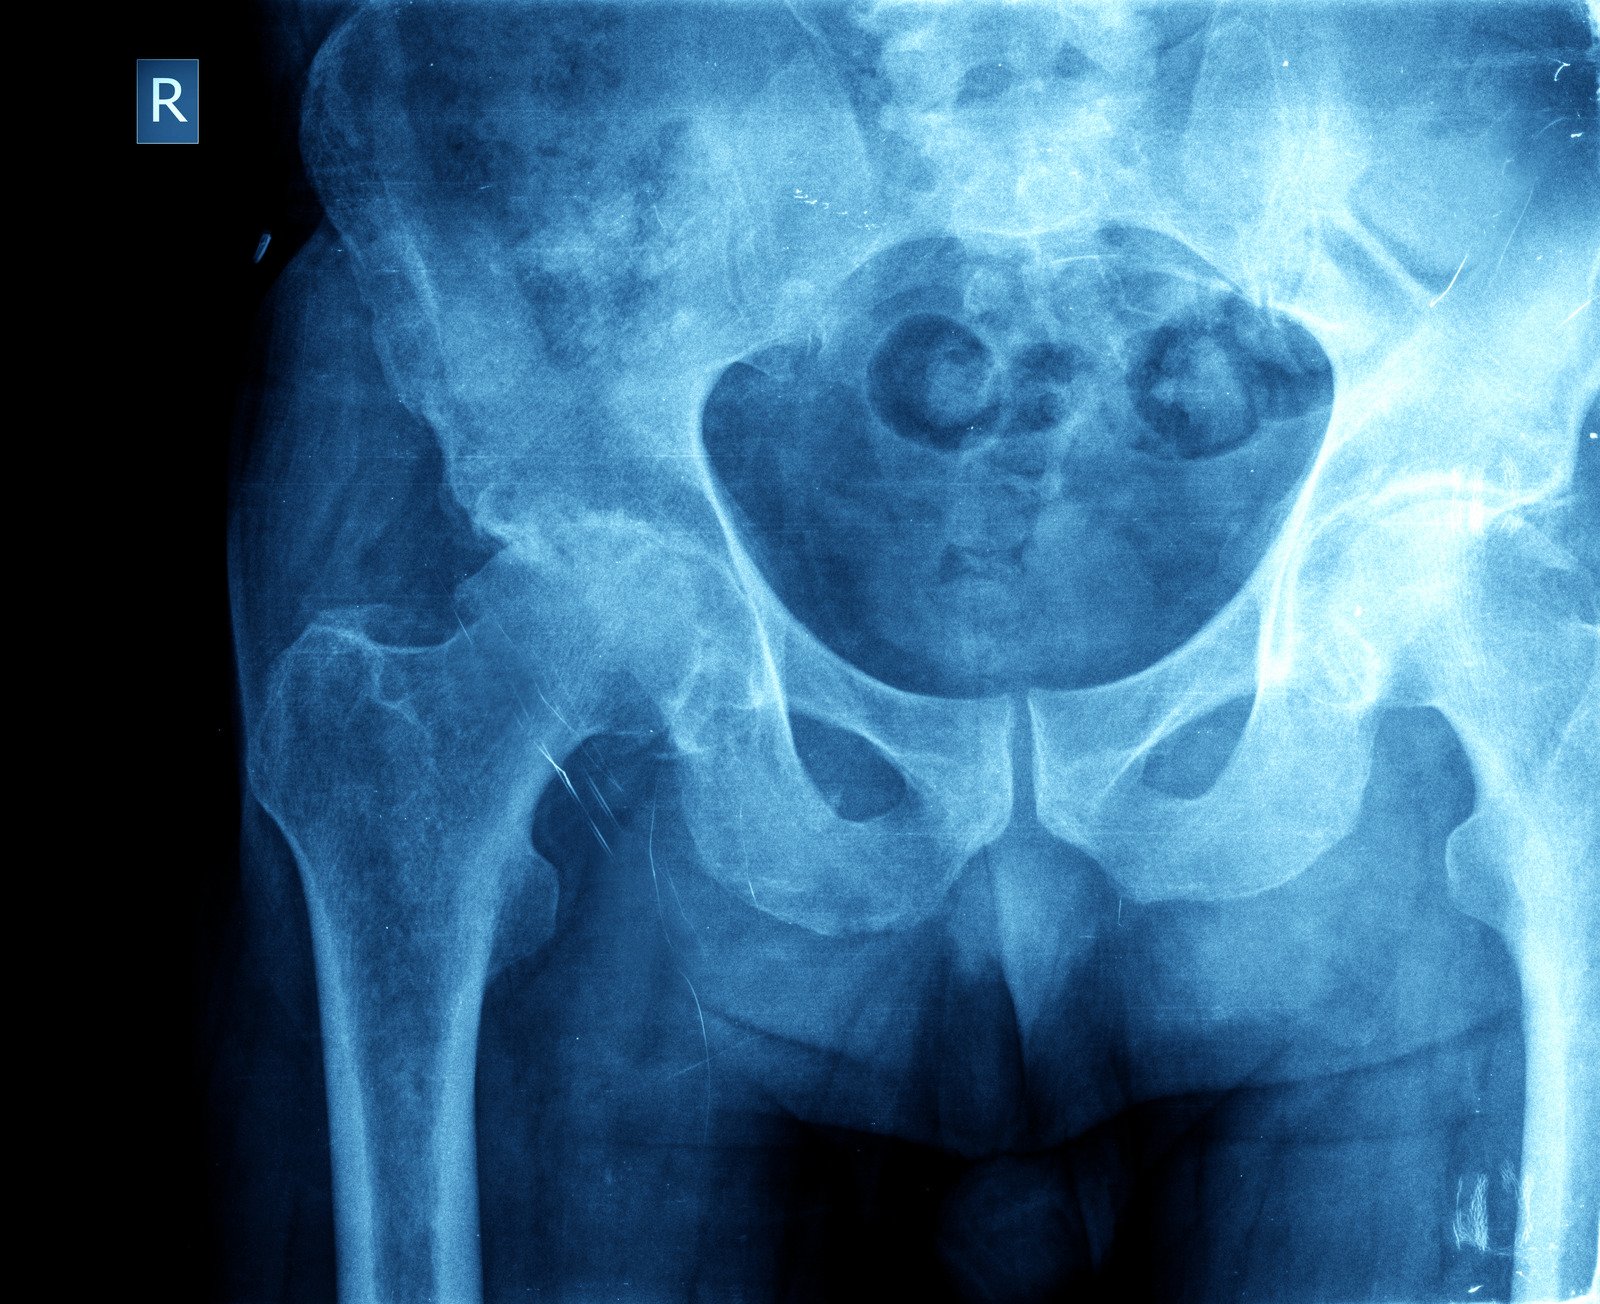

고관절 골절

정의

고관절 골절은 대퇴골(넓적다리뼈)과 골반을 연결하는 부위에서 뼈가 부러지는 부상을 의미합니다. 주로 대퇴골 경부와 대퇴골 전자부에서 발생합니다.